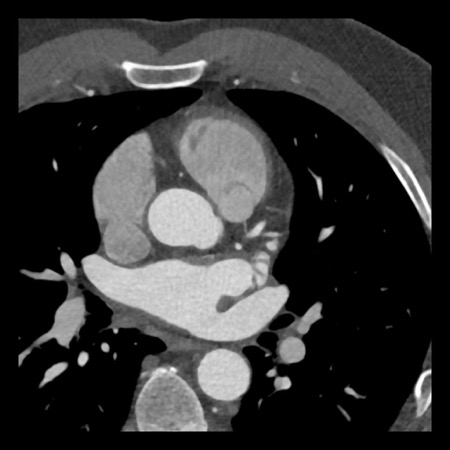

case 4 – CAD-RADS 3/P1/I+ thrombus left ventricle

First, scroll through the CTA images.

How would you describe the findings on the coronary CTA?

The findings are:

- Moderate (50-69%)

stenosis in the proximal LAD caused by a non-calcified plaque. - Variant of

sinoatrial (SA) nodal artery. The artery usually arises from the RCA as a second

branch after the conus artery, however in this case it arises from the LCX,

courses behind the aorta, anastomosing with the right atrium and with a small

branch supplies the SA-node of the heart. - Thrombus in the

apex of the left ventricle. - CTP was performed

in this patient. CTP showed a perfusion defect at stress imaging in the

territory of the LAD (I+), at rest no perfusion defect was visible.

This patient classifies as CAD-RADS 3/P1/I+, which means

this patient requires further investigation.